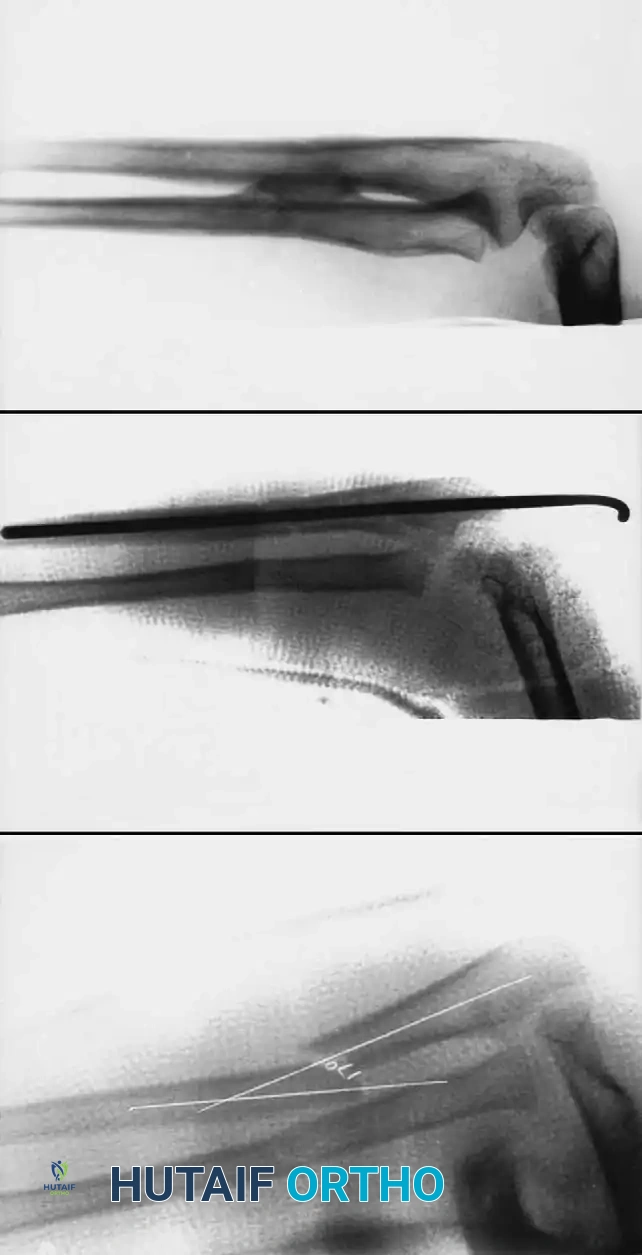

Step-by-Step Surgical Technique:

1. Positioning: The patient is placed supine with the arm extended on a radiolucent hand table. Fluoroscopy is positioned perpendicular to the arm.

2. Ulnar Nailing:

* An incision is made over the lateral aspect of the proximal ulna, 1-2 cm distal to the olecranon apophysis.

* The cortex is breached with an awl or drill.

* The pre-bent nail (contoured to create a bow that will tension against the inner cortices) is advanced antegrade down the ulnar shaft to the fracture site.

3. Radial Nailing:

* An incision is made laterally over the distal radius metaphysis, carefully avoiding the superficial branch of the radial nerve and the physis.

* The entry point is created, and the pre-bent nail is advanced retrograde.

4. Fracture Reduction and Nail Passage:

* Closed reduction is performed. The nails are advanced across the fracture sites under fluoroscopic guidance.

* If closed reduction is impossible due to interposition (often seen when initial translation exceeds 100%), a mini-open incision (1-2 cm) is made directly over the fracture to clear the soft tissue.

5. Final Seating: The nails are advanced to the opposite metaphyses. The trailing ends are cut, leaving 1-2 cm outside the bone but buried beneath the skin to facilitate future removal.